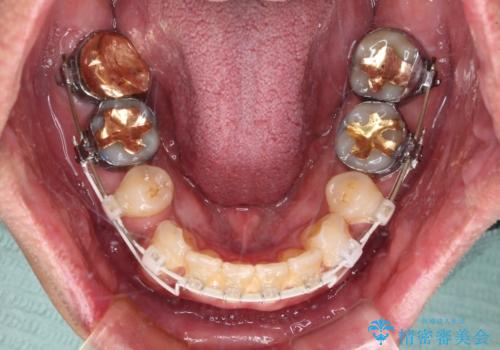

- 審美装置

- 口元の突出感を気にして来院された患者様です。

強い咬合力と上顎前歯の傾斜により前歯が突出し、唇が閉じにくい状況であったため、上下左右の第一小臼歯4本を抜歯し、ワイヤー装置にて矯正治療を行うこととしました。

非常に咬合力が強いため、抜歯したスペースが閉じるのか不安でしたが、順調に歯が移動し、予定よりも早く治療を終えることができました。